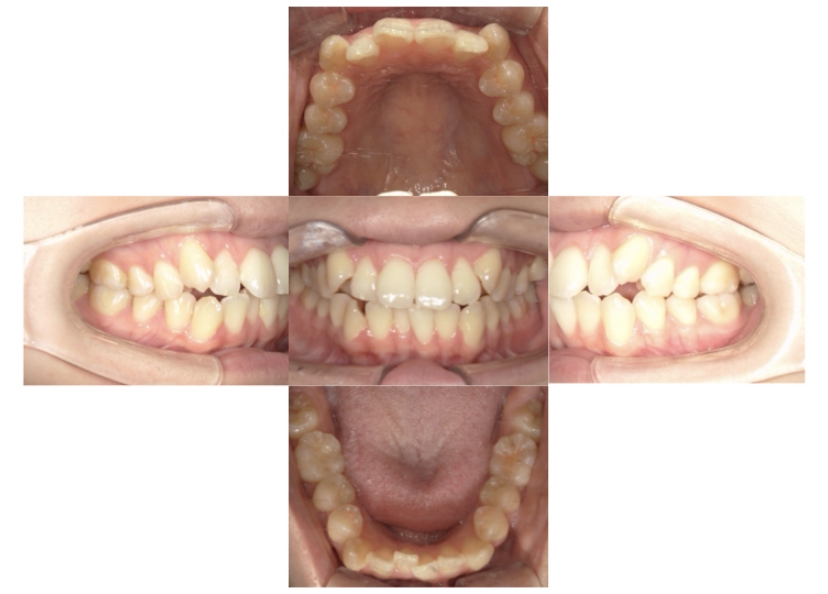

BEFORE

AFTER

上顎前突、叢生

抜歯

ブラケット矯正

上下顎叢生、上顎前突(出っ歯、上下の前歯のガタガタ)のケースです。

装置はラビアル(上下表側)で、上顎の小臼歯を2本抜歯を行っています。抜歯したスペースを使って、上の前歯の後方移動と叢生(ガタガタ)と出っ歯の改善を行っています。下は歯と歯の間にIPR(隣接面削合)を行い、スペースを確保し、叢生の改善を行っています。

主訴 前歯のガタガタと出っ歯が気になる。

年齢・性別 47歳 女性

お住まいの地域 神奈川県川崎市

治療方針 抜歯スペースおよびIPRを利用して上前歯の叢生(ガタガタ)の改善

抜歯部位 上顎左右第一小臼歯

使用装置 ラビアル(上下表側)、顎間ゴム

治療期間 2年0か月

治療回数 15回

リテーナー クリアリテーナー